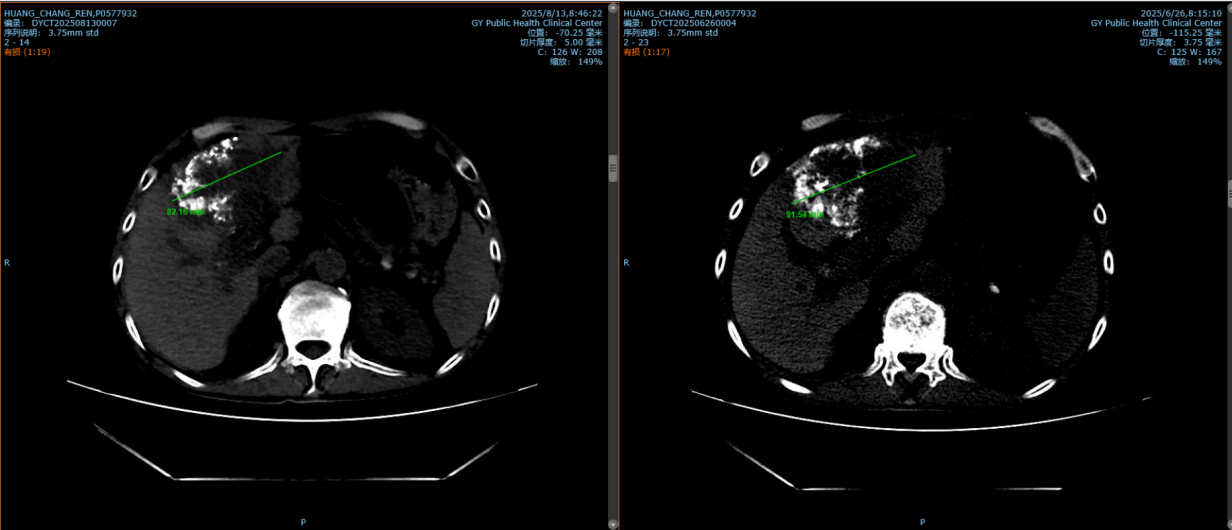

圖1:右側(cè)為第一次TACE術(shù)后病灶直徑約6cm,左側(cè)為此次HAIC術(shù)后病灶縮小約1cm。